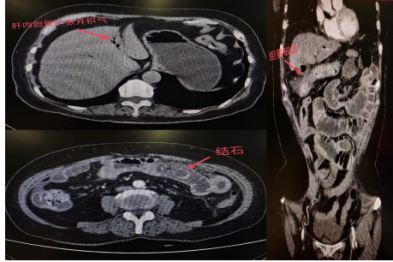

胆囊结石忍了又忍,这次撑破胆囊掉进小肠卡死